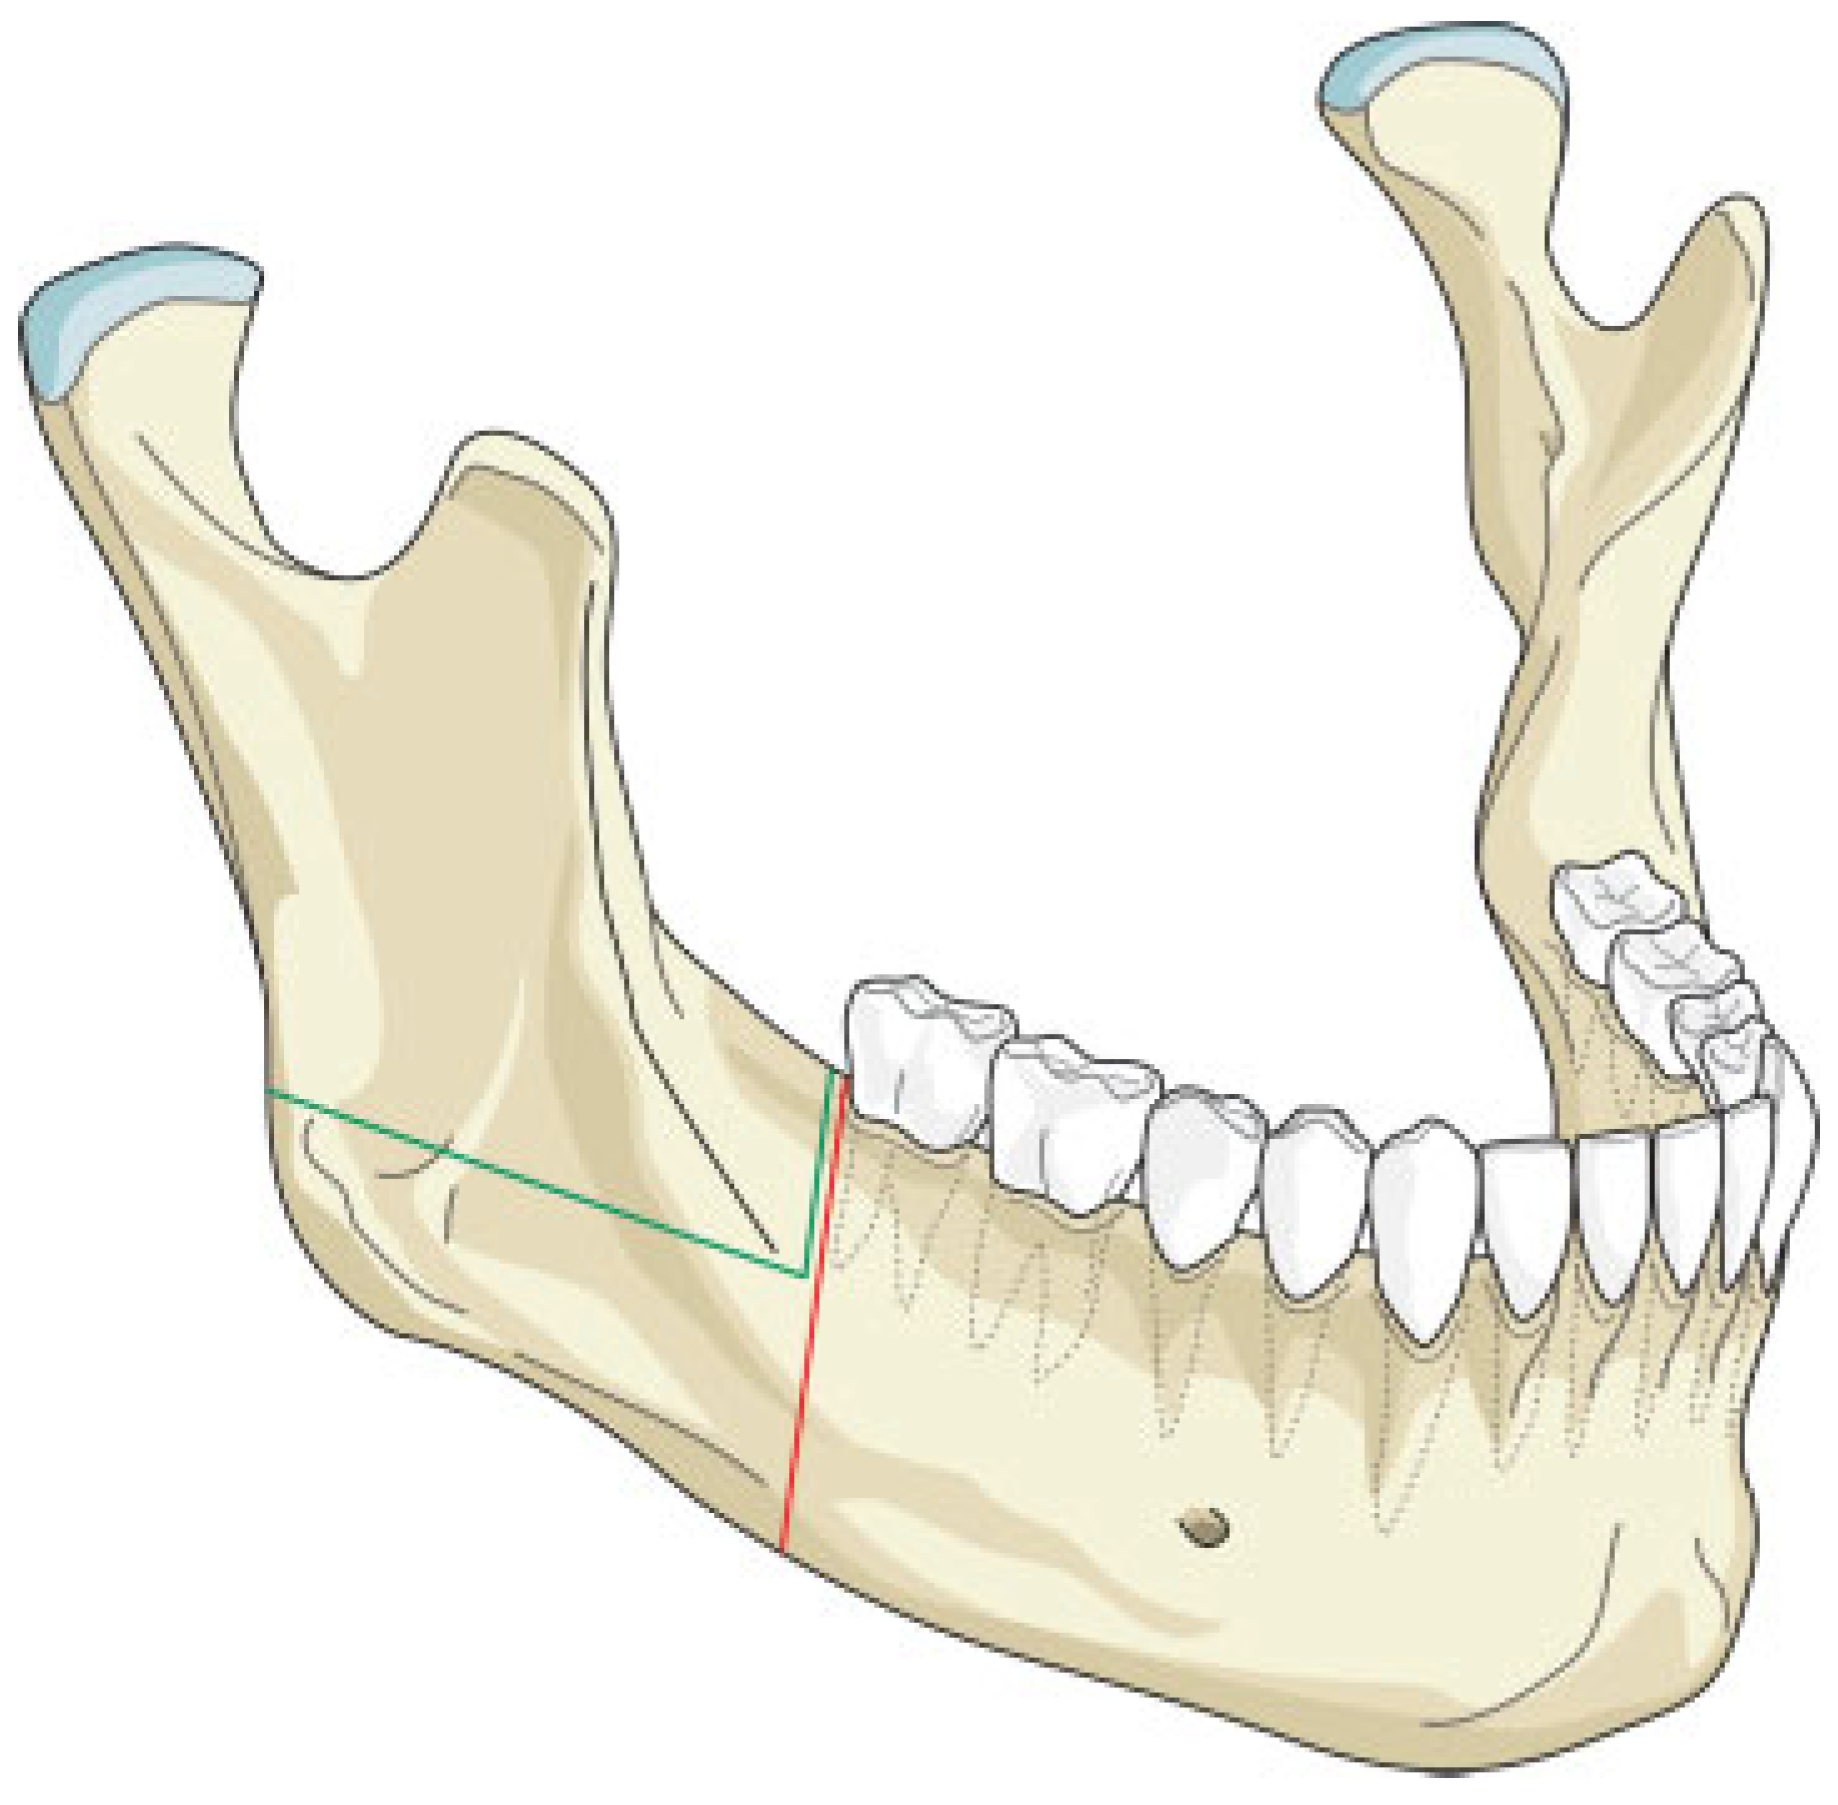

The mandibular resection is performed utilizing a horizontal osteotomy (Figure 1) above the mandibular angle on one side and a stepped body or angle osteotomy on the other side (Figure 2). A silicone template is created to the shape and dimension of the resected mandibular segment. The template is used as a guide to osteotomize the fibula at the donor site to reproduce the middle symphyseal segment of the mandible without shortening the fibula. The flap is then transferred to the recipient site and oriented so that one end will fit in the stepped osteotomy in a key and lock fashion (Figure 3) and the other end of the flap will overlap with the horizontal mandibular osteotomy (Figure 4), allowing room for adjustment in the anterior posterior direction to achieve the desired chin point projection (Figure 5). When the desired projection is achieved—guided by the silicone template—both ends of the flap are marked with a sterile pencil and trimmed using the saw; then miniplates are used to fix the flap in place (Figure 6).

Our technique is unique as it allows flexibility in adjusting the chin point projection to give the best possible aesthetic outcome. Trimming of the flap ends is performed at the recipient site to reduce the risk of short flap, but should this happen, the overlap at the horizontal osteotomy side will allow for compensation (Figure 4). Moreover, the greater surface contact area at the horizontal osteotomy side together with the key and lock fitting at the stepped osteotomy side (Figure 3) increase the stability of the flap and reduce the risk of rotation, hence allowing the use of miniplates for fixation; this in return allows room for placing more than one plate on each side, adding to the stability. The use of miniplates for fixation also facilitates the placement of implants in future rehabilitation.

Figure 2. Illustration of the stepped osteotomy cuts (black lines). The red lines represent the conventional osteotomy cuts without the modification.